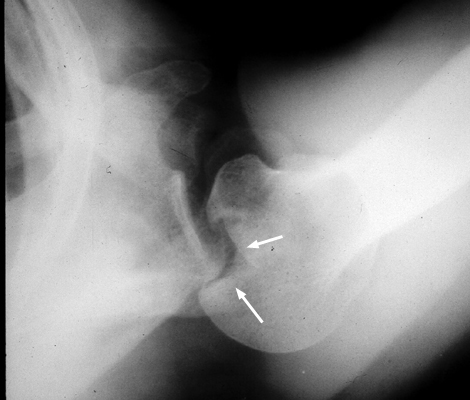

Diagnosis:Posterior shoulder dislocation Discussion:Trough line is seen with posterior shoulder dislocation. When the humeral head is forced posteriorly in internal rotation, the anterior aspect of the humeral head is driven against the posterior glenoid rim. With sufficient force, the head will sustain a compression fracture. In many cases of posterior dislocation of the shoulder, two parallel lines of cortical bone can be seen. The outer (more medial) cortical line represent the medial cortex of the humeral head, while the other line represents the margin of a "trough" like impaction fracture. References: